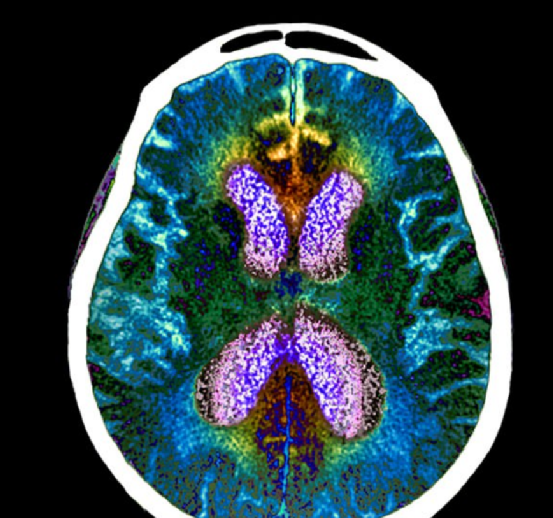

阿尔茨海默病,俗称“老年痴呆症”,是一种神经退行性疾病。人类发现这个疾病其实已经很早了。1906年,德国精神科医师及神经病理学家爱罗斯·阿尔茨海默(Alois Alzheimer)最先发表了“老年痴呆症”病例,后来就有了以他名字命名的阿尔茨海默症(Alzheimer’s disease, AD)

百余年来,阿尔茨海默病已经成为威胁人类尤其是老年人健康的一个主要病症,而且至今人类并未揭开其神秘面纱。